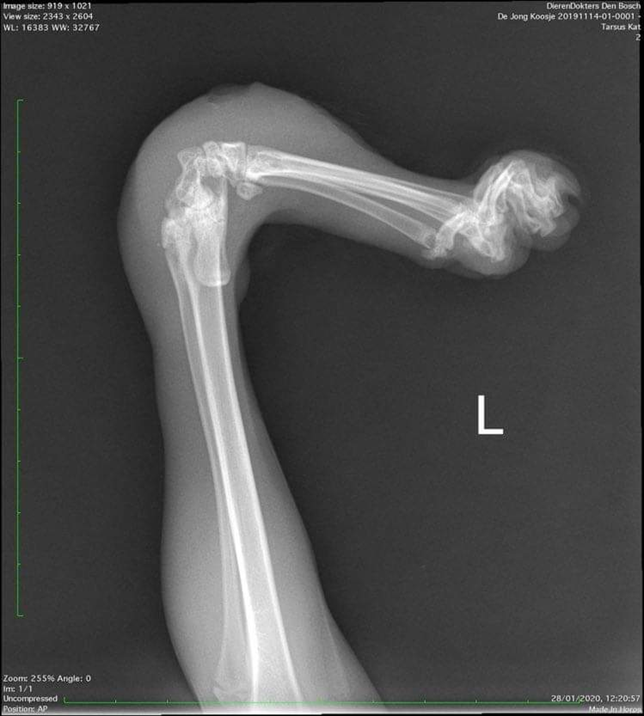

Un vétérinaire a diagnostiqué une affection appelée « Twisted Legs » – une déformation difficile à corriger sans chirurgie. Arianne s’est mise en quête d’un chirurgien. Elle en a trouvé un qui a accepté d’opérer Koosje lorsqu’il aurait onze mois et serait devenu adulte. D’ici là, Arianne devait s’efforcer de maintenir Koosje en vie.

Parce que Koosje marchait sur ses coudes, il avait de plus en plus de petites blessures malgré les magnifiques chaussettes avec semelles intérieures tricotées par une voisine. Cela nécessitait un traitement antibiotique constant. Un orthopédiste animalier a fourni à Koosje des orthèses, mais les plaies ne guérissaient toujours pas correctement. Lorsque Koosje a eu dix mois, Arianne a contacté le chirurgien. C’était devenu insoutenable et Koosje devait vraiment être opéré plus tôt. Elle a pris rendez-vous et Koosje a été examiné à nouveau. Mais une mauvaise nouvelle est survenue immédiatement : l’opération était trop compliquée et Koosje ne pouvait pas être opéré.

Mais l’euthanasie pour Koosje n’était pas une option ! Ce petit trésor aimait trop la vie. C’est alors qu’Arianne est entrée en contact avec la spécialiste Bouvien Brocks. Elle avait une excellente nouvelle ! Elle connaissait en effet une manière de guérir les blessures de Koosje en une semaine, mais a précisé qu’une opération était nécessaire. Et elle était prête à effectuer cette opération. Koosje a finalement subi plusieurs opérations lourdes, et elles ont toutes été couronnées de succès. Un peu moins d’un an plus tard, les pattes de Koosje étaient à nouveau complètement droites, et le petit chat pouvait à nouveau marcher sur ses quatre pattes. Maintenant, Koosje gambade à nouveau joyeusement et en pleine santé à la Maison des Chats. Et c’est là qu’il pourra rester pour toujours. Heureusement, car tout le monde est fou de ce petit chat courageux et robuste !